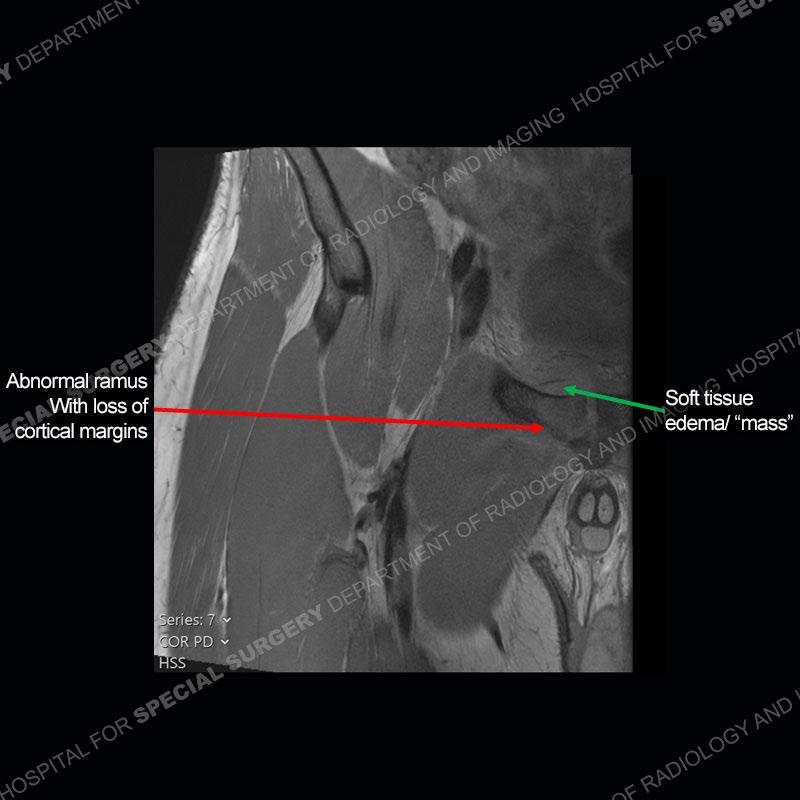

Radiographs did not demonstrate any clear abnormality. The MRI shows markedly abnormal signal of the right superior pubic ramus and abnormal signal/”mass” extending into the adjacent soft tissue. The inferior articular surface of the ramus showed what was thought to be bony destruction. CT examination shows a destructive process of the right superior pubic ramus.

Subsequent MRI in a very short time interval shows markedly increased abnormality of the ramus and increased edema and “mass” of the soft tissue. Post contrast imaging shows multiple, rim enhancing collections of the soft tissue and similar albeit less conspicuous enhancing collection of the ramus.